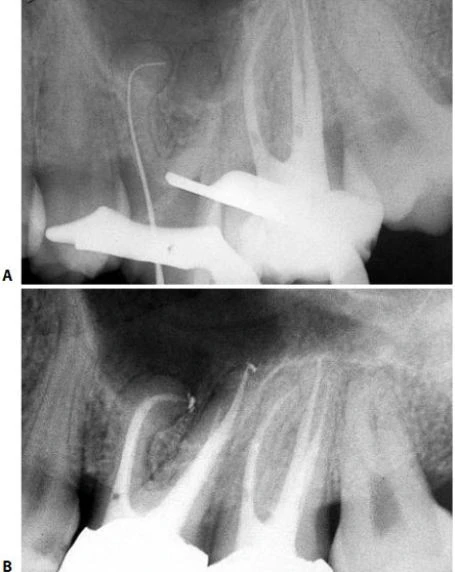

Về mặt giải phẫu học, răng cối nhỏ thứ nhất trên có thể có hình dạng hoàn toàn khác. Ống tủy cong hình lưỡi lê ở 1/3 chóp chân răng là một dạng điển hình. Hiếm khi tìm thấy một ống tủy đơn, hình elip trong một chân răng; thường gặp hai ống tủy giao nhau ở 1/3 giữa với hai lỗ chóp trong một chân răng (38%) hoặc hai ống tủy (thường cùng chiều dài) ở trong hai chân răng riêng biệt (60%). Hiếm hơn nữa có thể thấy ba chân răng với ba ống tủy và những lỗ chóp riêng biệt, chiếm 6% theo Carns và Skidmore , và 5% theo những tác giả khác. Trong những trường hợp này, RCN có hình dạng như răng cối lớn. Một ống tủy rộng hơn ở phía trong và hai ống nhỏ hơn ở phía ngoài, một ở phía gần và một ở phía xa (hình 11.46). Điều trị nội nha tốt hay không phụ thuộc vào việc tạo xoang tủy có đúng hay không: răng cối nhỏ trên với ba ống tủy thì cần tạo một xoang tủy có hình dạng chữ “T” với sự mở rộng theo chiều gần xa ở phần ngoài của xoang truyền thống. Sự thay đổi này cho phép tạo một đường vào tốt cho cả hai ống tủy ngoài. Nếu ba chân răng phân kỳ, ta có thể thấy được trên phim X-quang trước điều trị. Nếu ba chân răng chụm hoặc chồng lên nhau (hình 11.47A), ta có thể biết được trong lúc điều trị. Nha sĩ có thể nghi ngờ có hai ống tủy ngoài không chỉ nhờ vào sự hiện diện của 2 miệng ống tủy (thường không nhận ra hai miệng ống tủy riêng biệt), mà còn nhờ vào hướng của cây trâm thăm dò khi nó đi vào một trong hai ống tủy, hoặc hình dung trên phim X-quang thấy hình ảnh dị dạng nhưng những đường nét chung của chân răng vẫn bình thường [ví dụ: hoàn toàn nằm về phía gần (hình11.47 B)], ta có thể nghi ngờ còn một ống tủy ngoài thứ hai nữa mà hướng của nó nằm về phía xa hơn so với ống thứ nhất (hình 11.47 C, D).

Hình 11.46. A. Phim sau điều trị của răng #14 với ba ống tủy ở ba chân răng khác nhau. B. Trên cùng một bệnh nhân,hình ảnh X-quang răng #24. C. Hình ảnh X-quang trước điều trị của răng #24 với hình ảnh chân răng chồng lên nhau. D. Một góc chụp khác sau điều trị cho thấy hình ảnh ba ống tủy trong ba chân riêng biệt. E. Sau hai năm. F. Phim sau điểu trị của răng #14. Răng có ba chân: chân trong thẳng, hai chân ngoài nghiêng xa. G. Sau 3,5 năm.

Hình 11.47. A. Phim trước điều trị răng #14: Chân răng chồng lên nhau, không dễ nhận ra ba ống tủy. B. Dụng cụ đầu tiên được đừa vào miệng ống tủy (dường như là ống ngoài), hình ảnh dụng cụ đi theo một hướng bất thường so với hình ảnh chân răng. Nhìn kỹ thấy nó chuyển hướng về phía gần: dụng cụ đã đi vào ống gần ngoài. C. Uốn cong dụng cụ về phía xa rồi đưa vào cùng miệng ống tủy này, nó tự động đi vào ống xa ngoài. D. 34 tháng sau, phim X-quang cho thấy sự hiện diện của ba ống tủy.

Nếu có sự chia chân phía mặt ngoài- do đó hiển nhiên là có sự hiện diện của hai ống tuỷ mà nhà lâm sàng không chẩn đoán được- thì có thể dẫn đến làm thủng chân răng khi sửa soạn chân răng để đặt chốt hay khi quay cement để gắn chốt (mà nhà lâm sàng cứ nghĩ rằng chỉ có một ống ngoài mà thôi!) (hình 11.48). Vì những lý do trên, nên luôn có quyết định tối ưu số lượng ống tủy cần điều trị, thậm chí nếu chỉ để tự trù thời gian cần cho việc điều trị.

Hình 11.48. Không chẩn đoán thấy sự chia chân và kết quả là làm thủng thành. A. Phim trước điều trị. B. Lật vạt và nhận thấy sự thủng thành. C. Chuẩn bị xoang để hàn chỗ thủng. D. Trám xoang bằng Super EBA. E. Phim sau điều trị. F. Sau hai năm. G. Hình ảnh lâm sàng sau hai năm.

Trong phục hình răng cối nhỏ, có thể gặp khó khăn trong quyết định ống tủy tìm được là ống trong hay ống ngoài. Tìm ống tủy còn lại sai hướng rất nguy hiểm và có thể dẫn đến thủng thành. Trong những trường hợp này, việc chẩn đoán rất dễ nếu dựa trên X-quang chụp theo một hướng khác và ứng dụng qui tắc “phía ngoài” (buccal object rule).